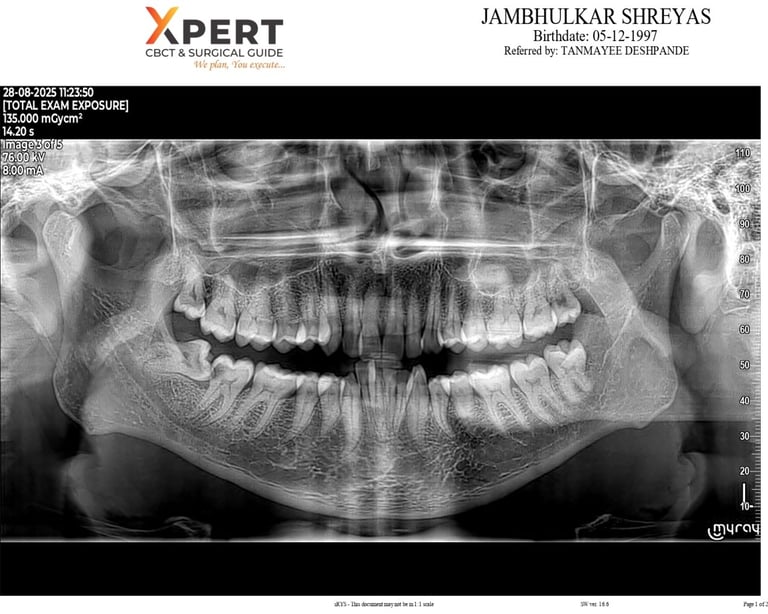

RADIOGRAPHS / X RAY / OPG- After detailed medical and personal history we take radiographs of single tooth, our clinic has RVG for radiographs it would take just 5 sec for each radiographs.